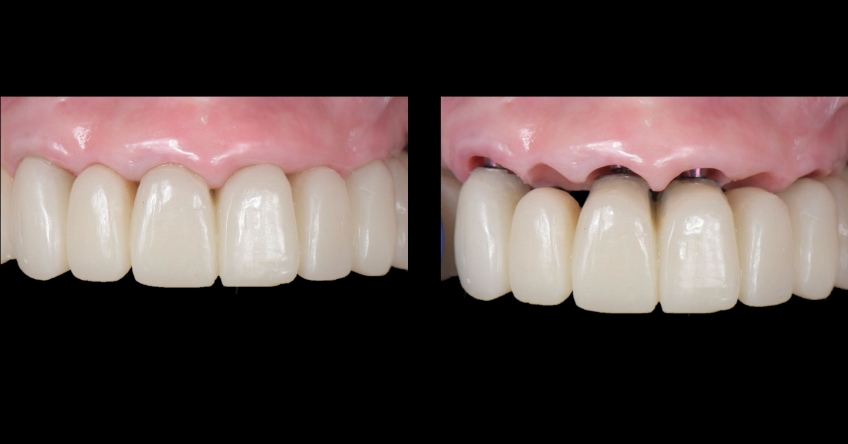

Our patient is a 66-year-old woman who presented with three remaining teeth in the maxillary arch and a fixed-hybrid temporary reconstruction in the mandible. She came looking for a second opinion regarding treating her maxillary arch.

Even though there were only three remaining teeth, they were so severely compromised that they were hopeless; however, their presence, as well as the support provided by the flipper type of removable provisional restoration, helped enormously in preserving a rather pleasing gingival architecture, which would be destroyed if we chose a fixed-hybrid restoration.

This makes her a lip-tooth-ridge Class I patient according to the published classification. According to Dr. Mish’s classification, she is an FPI, which means her preexisting condition is conducive for an all-white, implant-supported fixed dental prosthesis without any pink ceramics.

The challenge is that bone availability is limited to her premaxilla, so we must either graft the sinuses to incorporate distal implants or bypass the sinuses and place one ZI bilaterally. Both approaches are perfectly doable and predictable because they’re supported in the scientific peer-reviewed dental literature. They also present nuanced implications that need to be reviewed and understood by the treating team and the patient, who is the ultimate decision-maker.

Once the patient understood the nuances between graft vs. a graft-less solution, she opted for a combination of anterior and ZIs instead of grafting the sinuses.

Ultimately, the patient was treated using a combination of traditional and zygomatic implants, allowing her to transition into the definitive prosthesis uneventfully and in a reasonable time frame. This prosthetic design aimed to improve the distribution of occlusal forces and provide enhanced structural support for the final prosthesis.